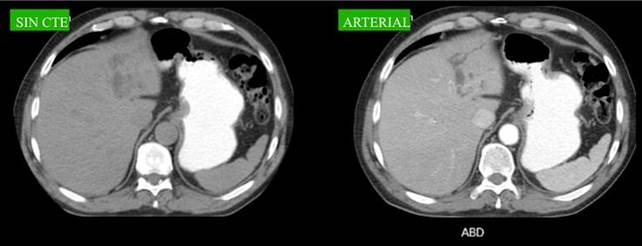

Debido al antecedente de pancreatitis aguda a repetición, se realiza TAC de abdomen y pelvis, la cual informa vía biliar intrahepática levemente dilatada a predominio del lóbulo izquierdo. Páncreas con aumento de tamaño, contornos mal definidos, múltiples colecciones líquidas hipodensas peripancreáticas.

Se decide realizar ColangioRMN, que informa en proyección de lóbulo hepático izquierdo, segmento III, formación quística ovoidea, hipointensa en T1, hiperintensa en T2, de 20 mm x 25 mm, que provoca obstrucción en sistema biliar intrahepático izquierdo con dilatación. Vesícula sin imágenes endoluminales. Páncreas con aumento de espesor y colecciones peripancreáticas. (Fig. 1,2)

Fig. 1 y 2: RMN:Vía biliar intrahepatica derecha normal. En proyección de lóbulo hepático izquierdo, segmento III, se visualiza una formación quística ovoidea, hipointensa en T1, hiperintensa en T2, de 20 mm x 25 mm, que provoca obstrucción en sistema biliar Intrahepatico izquierdo con dilatación. ¿Quiste biliar congénito?